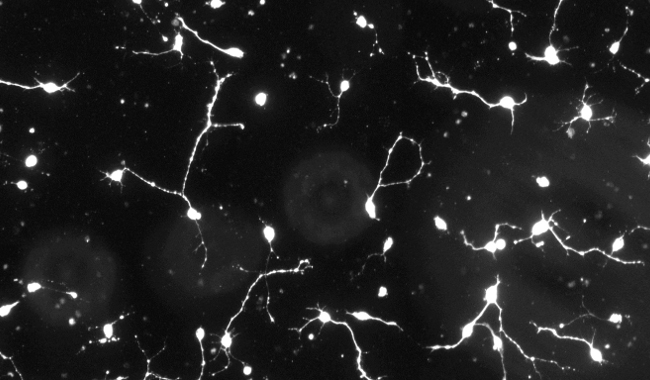

神經(jīng)突增生圖像分析

神經(jīng)系統(tǒng)是一個復(fù)雜的神經(jīng)元網(wǎng)絡(luò),它的正確運作高度依賴于神經(jīng)元向神經(jīng)元連接的適當發(fā)育;因此,神經(jīng)回路的形成非常依賴于突起生長過程的正確進化。突起生長是神經(jīng)突起形成和發(fā)展的復(fù)雜而關(guān)鍵的過程,其故障涉及一系列的神經(jīng)元疾病和疾病,如阿爾茨海默病和帕金森,因此它構(gòu)成了神經(jīng)病學(xué)和精神病學(xué)研究的主要焦點之一。